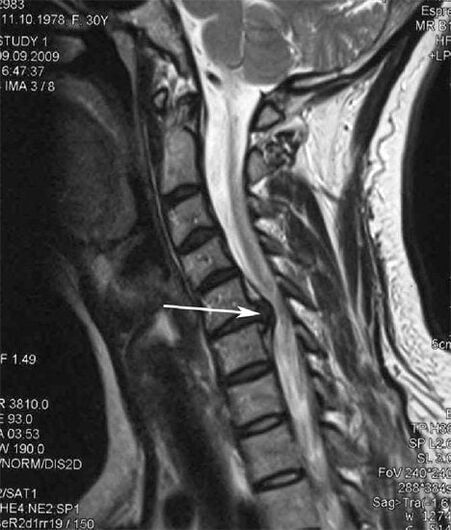

Στα αρχικά στάδια, η οστεοχόνδρωση ανιχνεύεται με μαγνητική τομογραφία. Αργότερα, η παθολογία μπορεί να διαγνωστεί χρησιμοποιώντας ακτινογραφία. Στις ακτινογραφίες της αυχενικής μοίρας της σπονδυλικής στήλης είναι αισθητή η μείωση της απόστασης μεταξύ των σπονδύλων, οι παθολογικές αλλαγές στις αρθρώσεις της όψης και η οστεοφυτία.